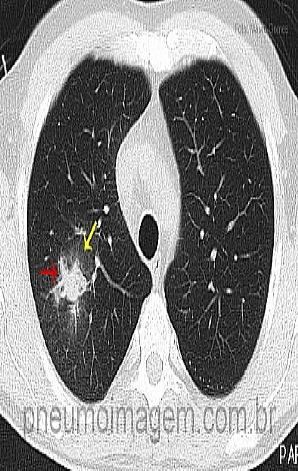

Veja imagens de Aspergilose Pulmonar Invasiva no PneumoImagem clicando aqui.